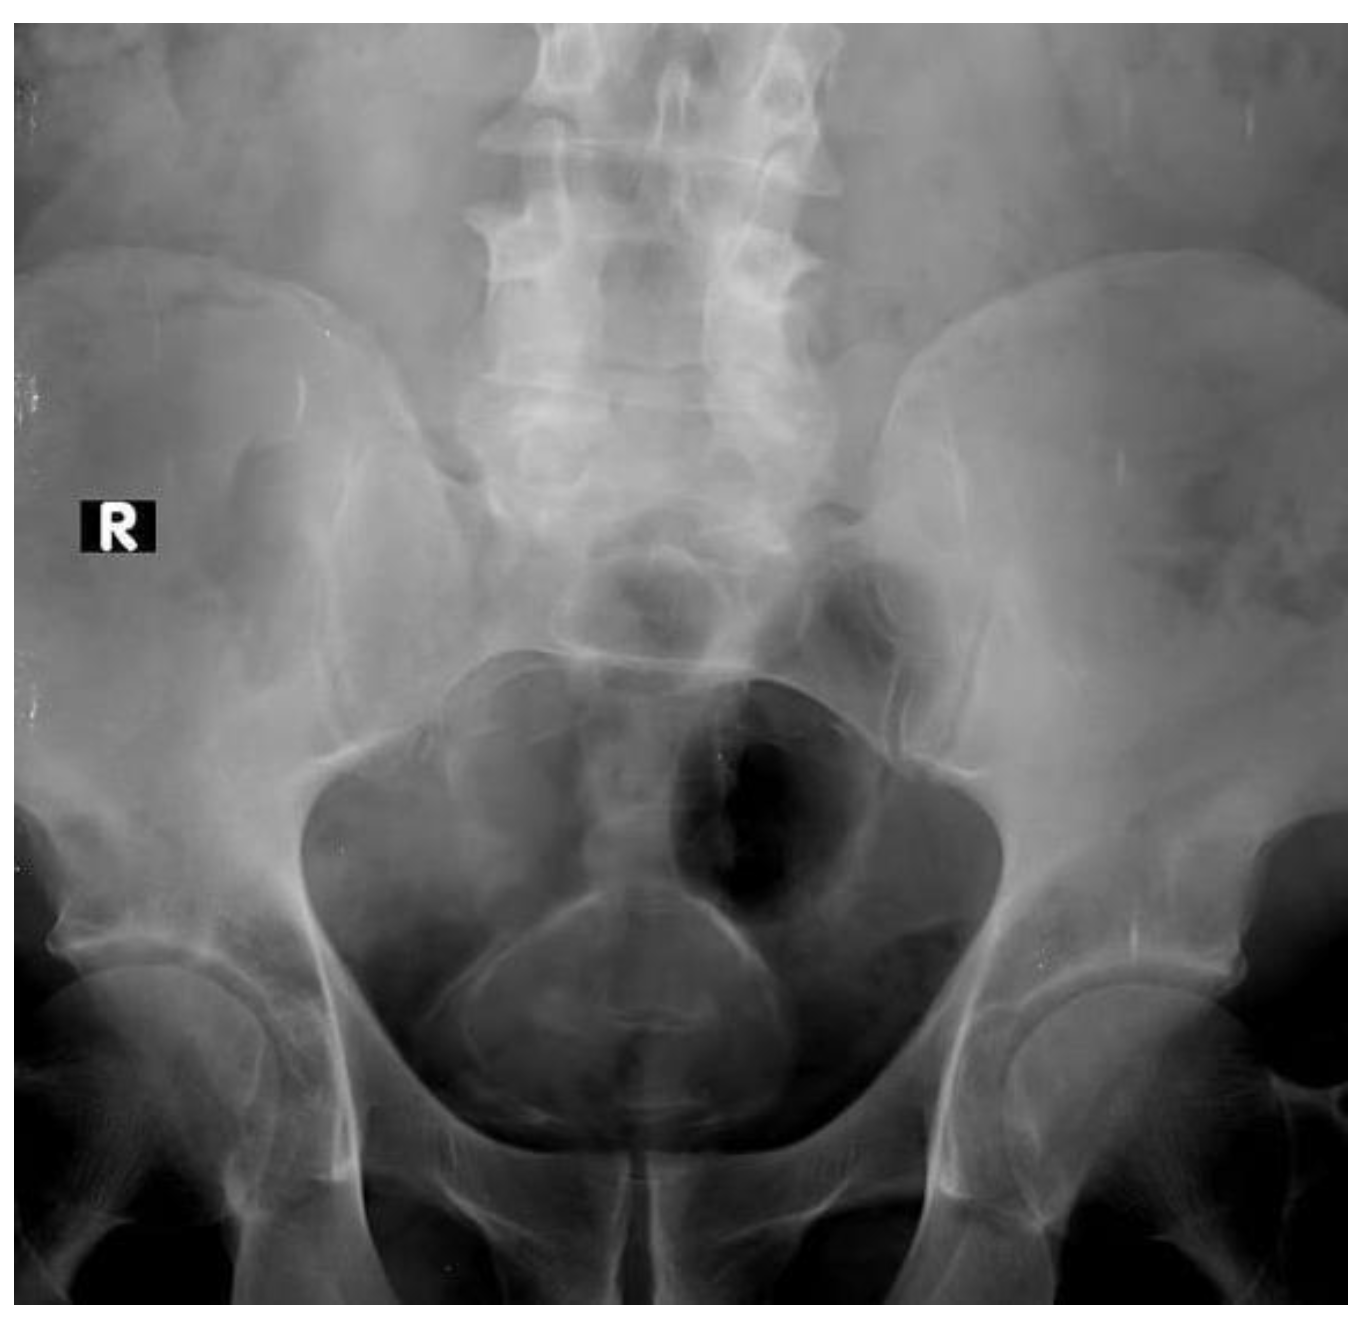

Supine Position Of Urinary Tract Xray Image Stock Photo – Download …

X-ray of Normal Kidney Ureter Bladder (Male) | Eccles Health Sciences …

Plain Kub Or Xray Image Of Urinary System Showing Kidney And Bladder …

Preoperative kidney, ureter, and bladder X-ray of patient. | Download …